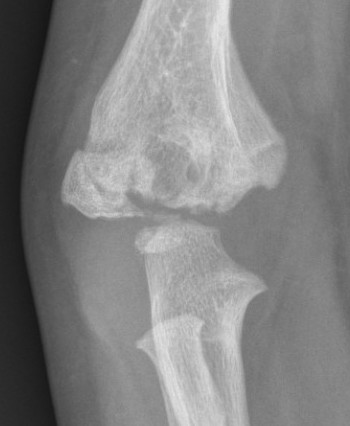

Complications

AVN post reduction and K wire in a 2 year old

- cubitus varus 19%

- AVN 4%